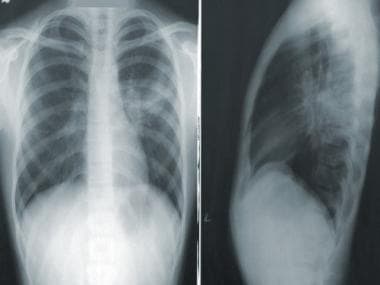

Representational image. CDC@Unsplash